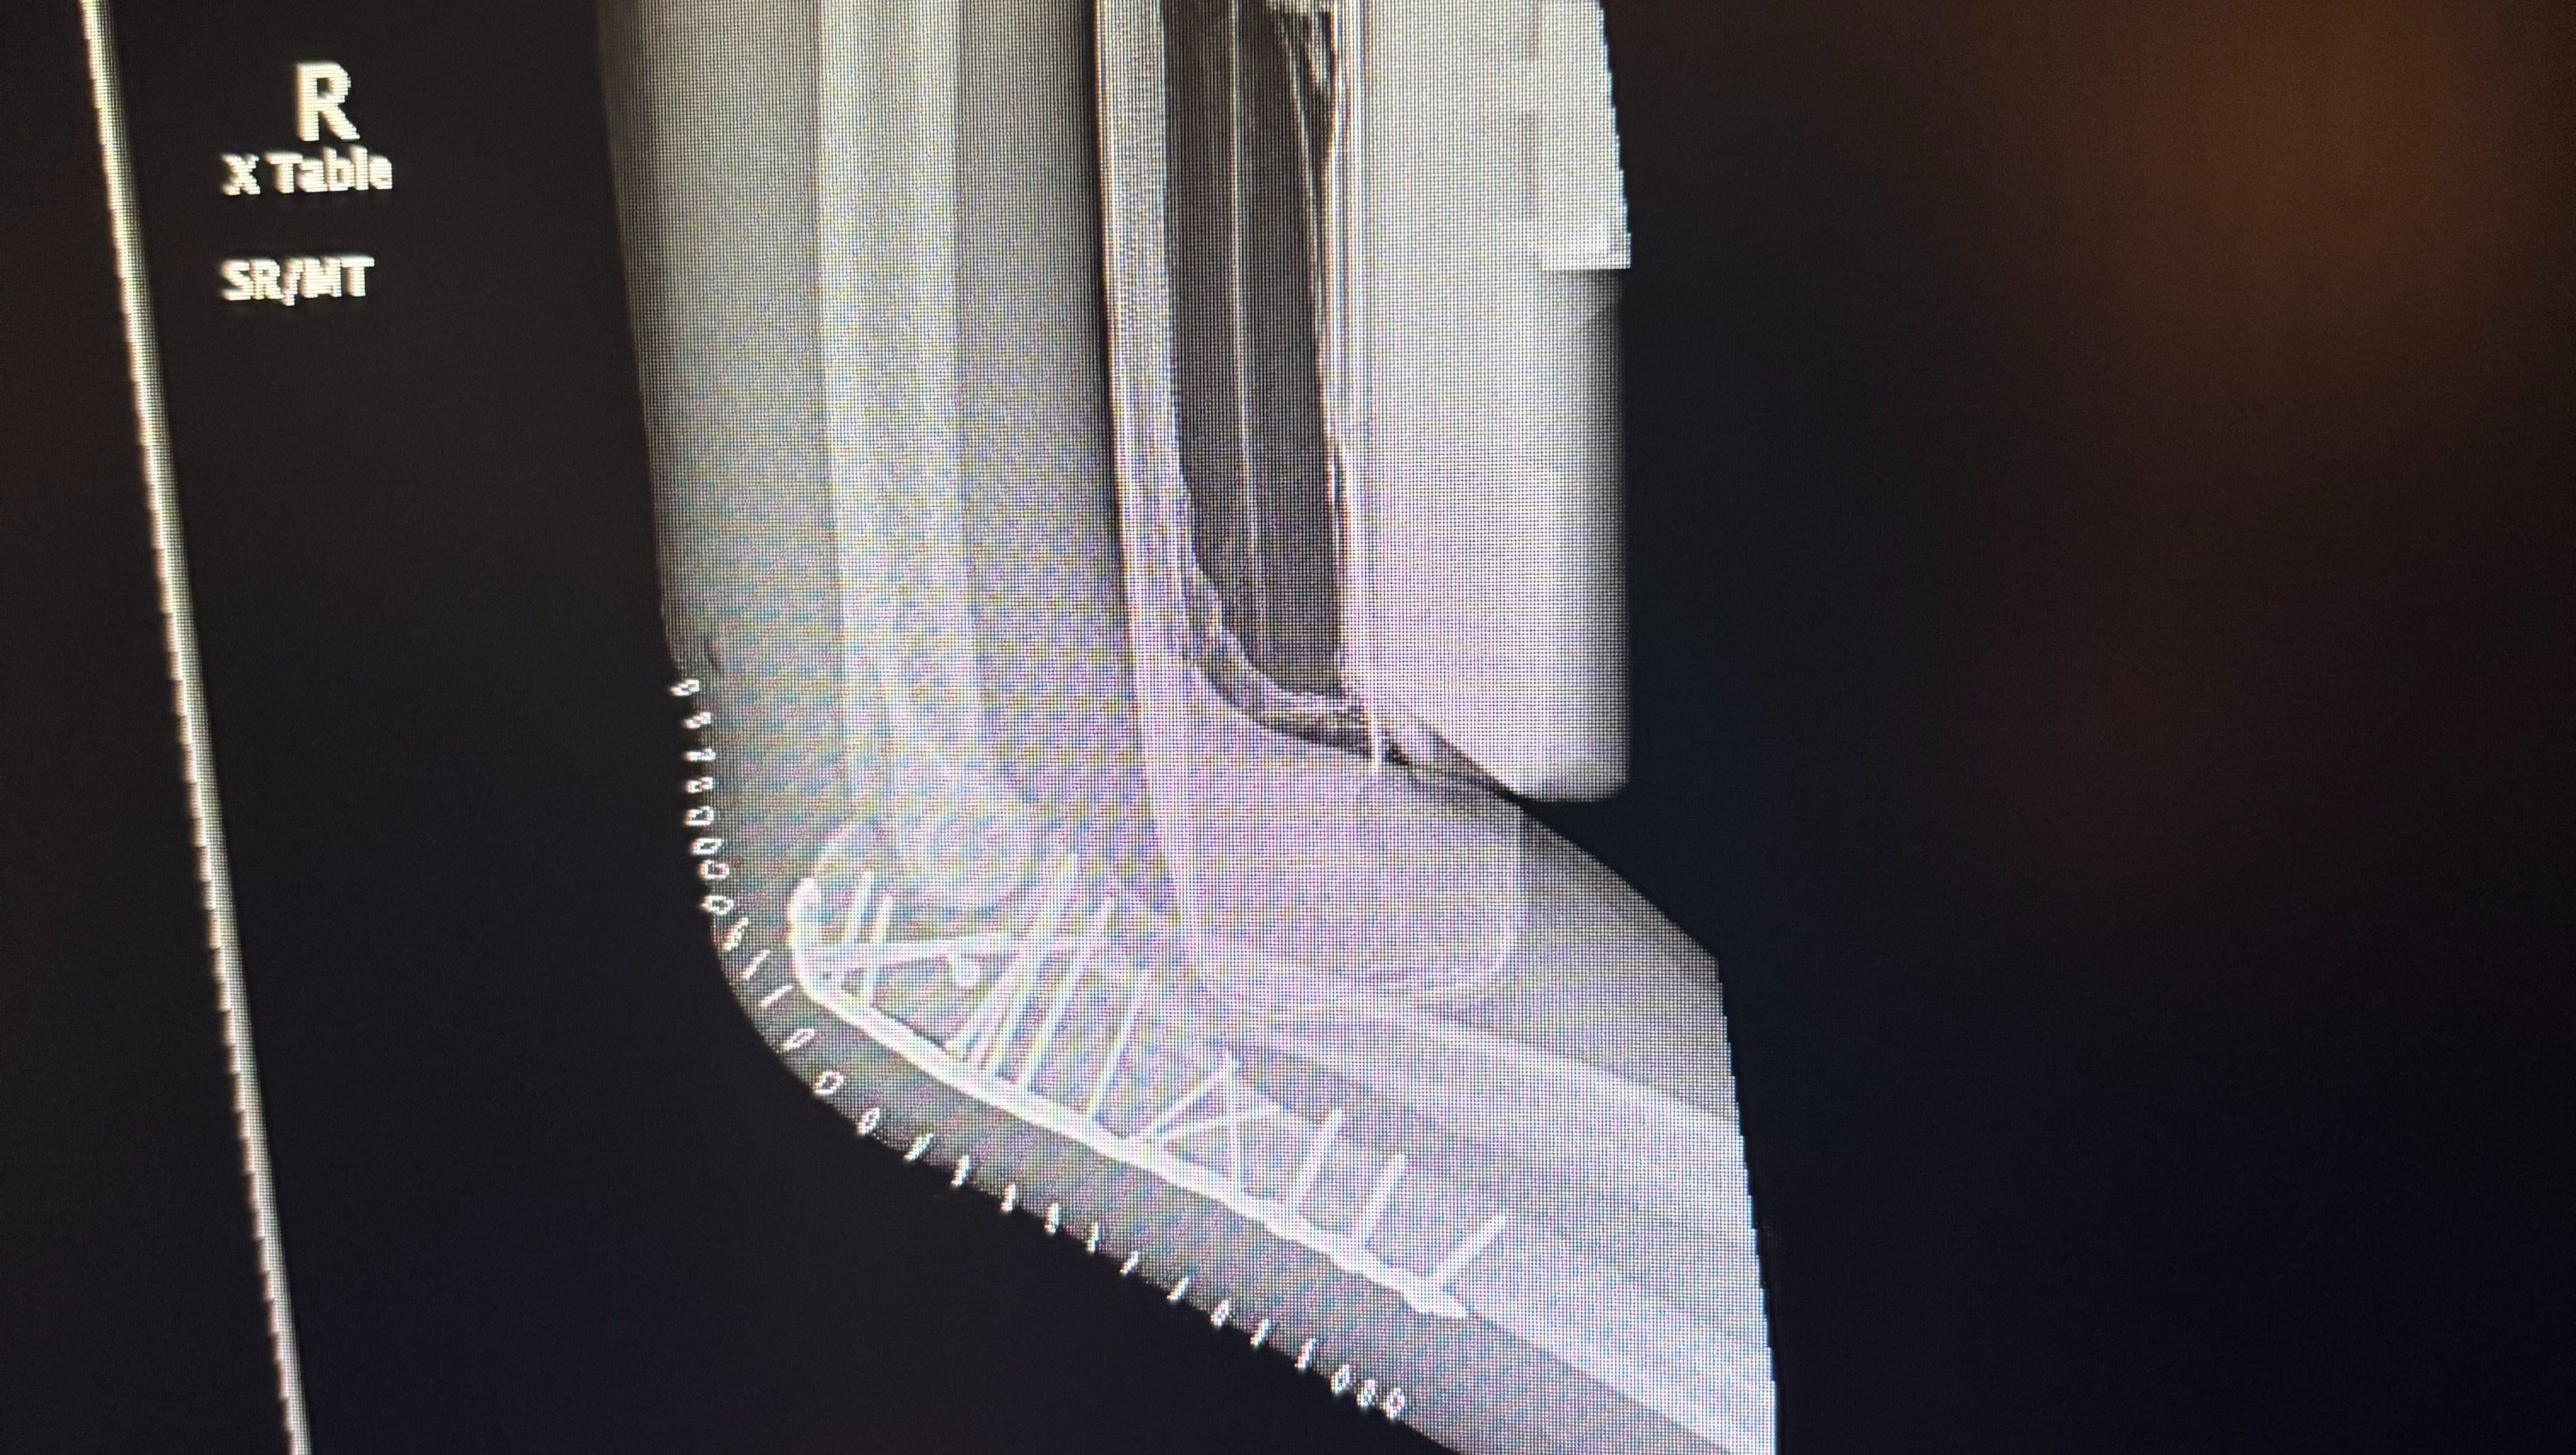

On the night of May 27th, 2024, Chad Day's life took an unexpected turn. A motorcycle accident left him with 15 screws in his right arm and a minor brain injury. Chad, a devoted father of two young boys, Thomas and Henry, aged 4 and 1, and his partner, Elizabeth, were suddenly thrust into a whirlwind of uncertainty. As if the physical and emotional toll weren't enough, the financial implications of the accident are overwhelming. Chad, self-employed and without health insurance, faces mounting medical bills and a temporary inability to work.